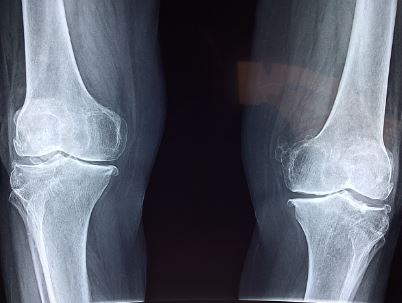

- 건강보험급여 '인공관절치환술 (슬관절)' 인정 기준에 준하는 환자